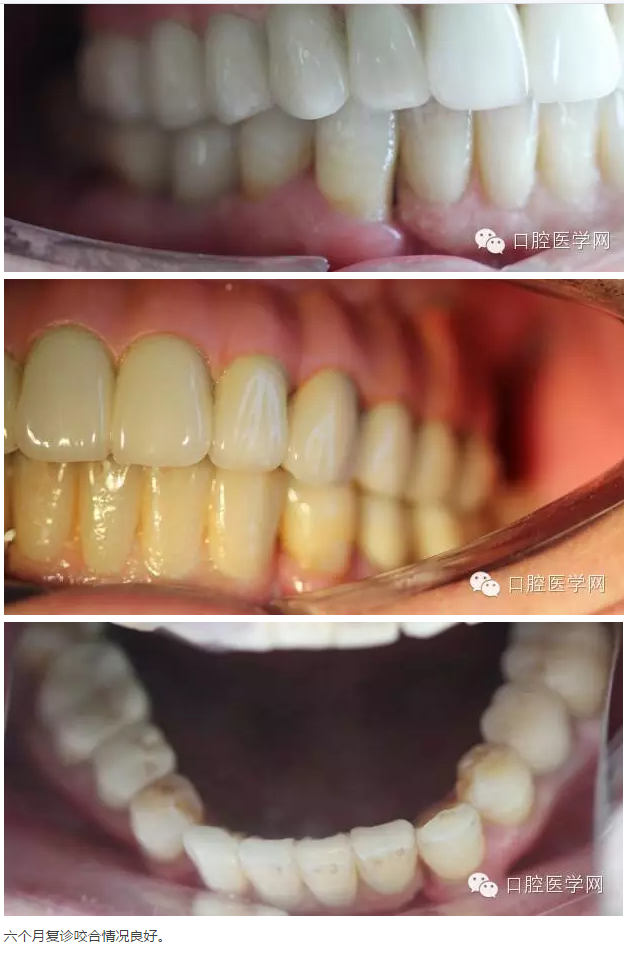

轉:口腔醫(yī)學網